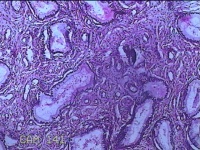

性别

女

年龄

44岁

临床诊断

宫颈赘生物

一般病史

发现宫颈赘生物2年余。

标本名称

宫颈组织

大体所见

灰白暗红色组织3.8x1.5x0.8cm一块,表面光滑,以宫颈12点缝线标记处切开,切面灰白粉红色,质软,宫颈3点处见灰白粉红色囊性肿物1.8x1.5x0.3cm一个,切开肿物,内见大量乳白色内容物,囊壁厚0.1cm。